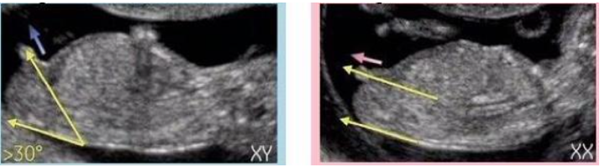

1、单子上的图像,男女宝宝有区别

NT单子上会有宝宝的图片,我们在图片上可以看到具有性征的一些身体特点,男孩的特征点与身体呈45度角,还多一些,而女孩儿的特征点几乎和躯体平行。还有就是如果是男宝宝,屁股位置会微微上翘,后背脊柱成圆弧状,因为要留空间发育前列腺,相反,女宝宝后背脊柱就相对就平一些。